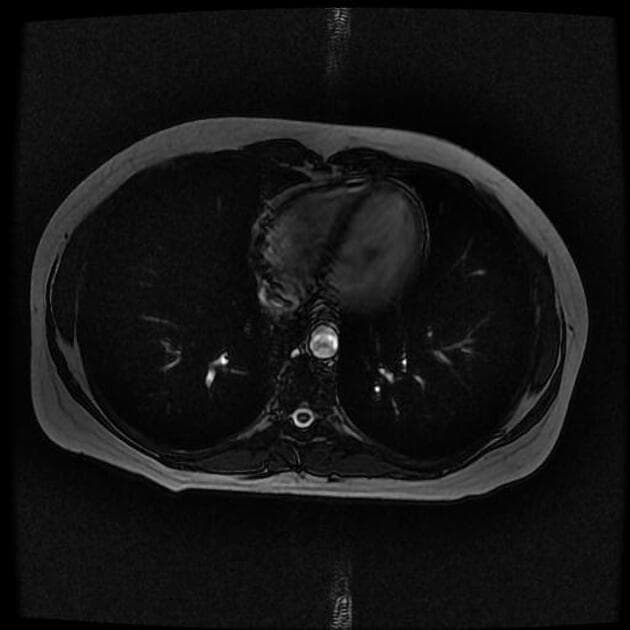

Chụp cộng hưởng từ theo dõi

Hai tổn thương khu trú ở gan được xác định:

Kết luận: Hai tổn thương khu trú ở gan, hình ảnh cộng hưởng từ phù hợp với tăng sản khu trú dạng nốt (focal nodular hyperplasia).

Hai tổn thương bắt thuốc ở phân đoạn 6 và 3, vùng trung tâm giảm tỷ trọng (không bắt thuốc) và không có hiện tượng thải thuốc (washout).

Hình ảnh điển hình của tăng sản khu trú dạng nốt (focal nodular hyperplasia), là một trong số ít các tổn thương có khả năng tích tụ mạnh thuốc cản quang đặc hiệu tế bào gan.

- "Trên hình ảnh thì gan-mật với Primovist, FNH thường giữ thuốc cản quang do sự hiện diện của tế bào gan hoạt động, giúp phân biệt với ung thư tế bào gan dạng tuyến."